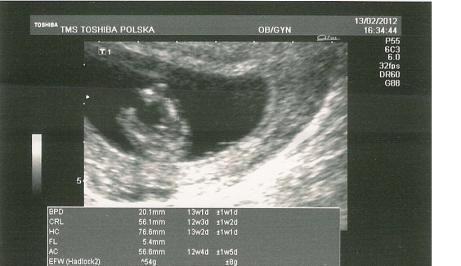

20 weeks Attachment 1883 12 weeks Attachment 1884 12 weeks Attachment 1885